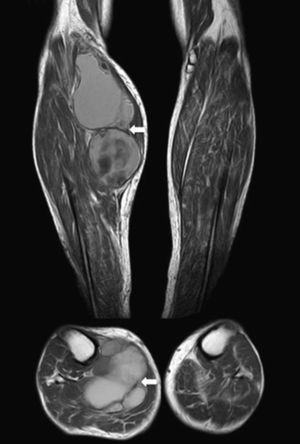

We present the case of an 83-year-old male patient with osteoarthritis, who came to the emergency room due to acute inflammation of the leg simulating DVT. On physical examination, there was a mass of elastic consistency, non-pulsatile, painful, in the popliteal fossa, extending to the leg (Fig. 1). The differential diagnosis was made with Baker cyst. The patient underwent, as a technique of choice, an ultrasound. The color Doppler mode showed patency of the deep venous system. Musculoskeletal ultrasound evidenced a well-defined collection, adjacent to the medial gastrocnemius muscle belly, full of vague echoes predominantly of low amplitude (Fig. 2) Despite being frequent, the size of the tumor made ultrasound insufficient and we decided to perform specific knee MRI with T1 potentiated sequences, T2* sequences (Figs. 3–5) and, after administration of intravenous contrast, we confirmed the existence of giant popliteal cyst of 17cm×9cm. The patient was treated conservatively, using, in the first place, nonsteroidal anti-inflammatory drugs, with clinical improvement and asymptomatic after the first 6 months. For this reason, along with the age of the patient and in spite of the cyst barely changing its size, surgical treatment has so far been dismissed.